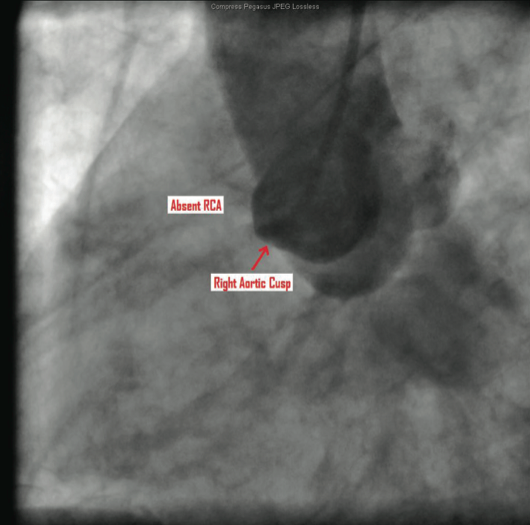

The catheterization and angiogram showed a patent left main coronary artery that bifurcated into the left anterior descending (LAD) and the left circumflex (LCX). The LAD had a mid 50% stenosis and the LCX was a large-sized vessel that gave off three obtuse marginal (OM) branches and continued distally into the right

side of the heart, filling the right coronary artery (RCA) from the distal end retrograde. The LCX had a mid 70-80% lesion that was confirmed by intravascular ultrasound (IVUS). The right coronary artery had no ostium and received retrograde filling via the LCX, continuing distally into the right myocardium. The LCX 80% mid stenosis was successfully revascularized with deployment of two drug-eluting stents. The patient was placed on post-procedure clopidogrel, simvastatin, beta blockers, and nitroglycerin.